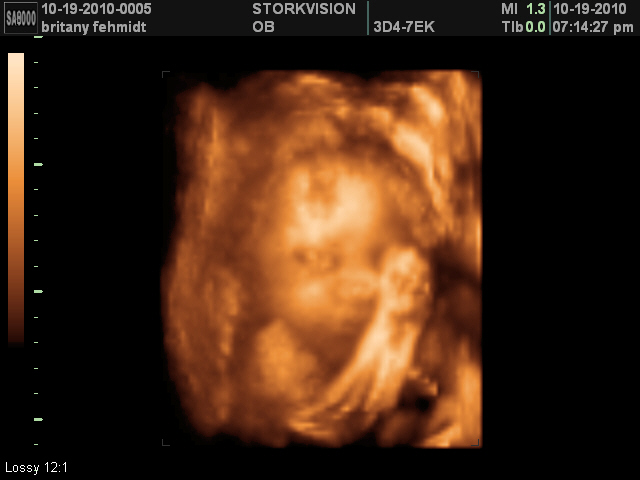

4D Sonogram

We had our 4D Ultrasound tonight... it was amazing! We all thought her nose and mouth looked like Aniston. Aniston was so cute, and sweet! I'm so glad she got to see it! She kept saying, "Awww she's so cute! Awww she's so sweet. My Baby sister is so cute!"